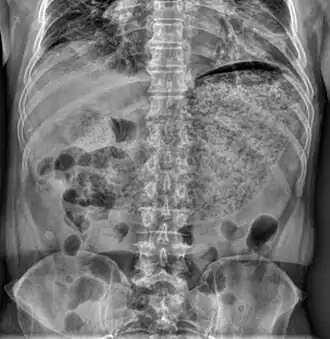

Гастропаре́з — расстройство пищеварения, характеризующееся снижением активности мышечного аппарата желудка.

Диагностика